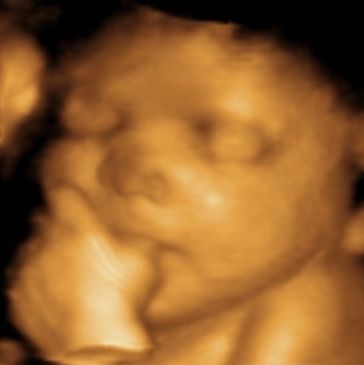

See your baby's growth more detailed than ever!